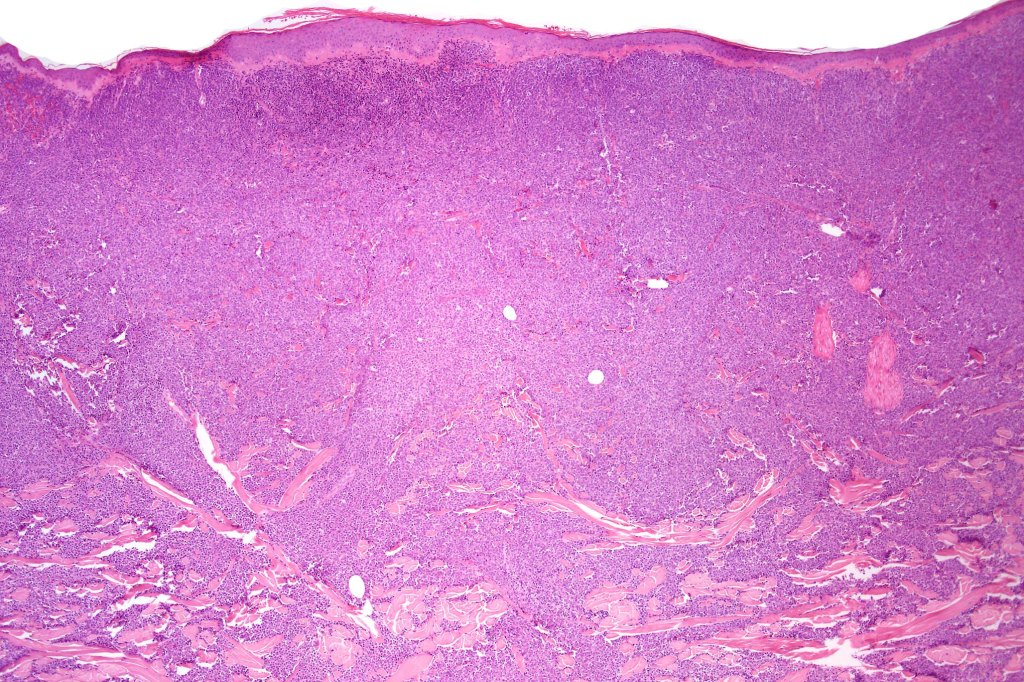

. No epidermal involvement

. Dermal +/- subcutaneous fat infiltrate

. Monotonous blast cells with gray-blue cytoplasm & irrregular vesicular nuclei with prominent nucleoli